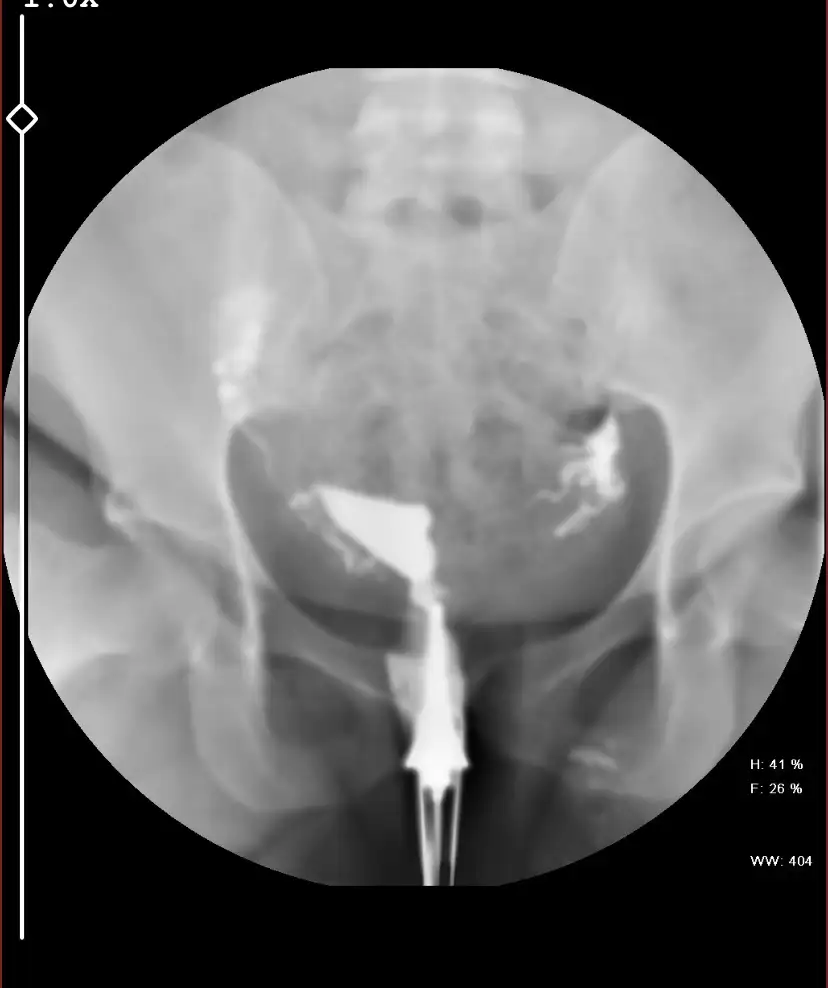

Zaten çeken kişiye sorunca söylüyor benim gördüğüm tek tüp tamamen açık,diğerinde varsa da tıkanıklık işlemden sonra açılmıştırHaklisin bende biliyorum. Ama korkudan zamanda gecmiyor belki anlayan olur diye sordum saol yinede

Soylemedi gicik biriydi ucgun sonra gel dedi oda bidaha carsambaya kaldi her gel dedi an gidemiyoruzZaten çeken kişiye sorunca söylüyor benim gördüğüm tek tüp tamamen açık,diğerinde varsa da tıkanıklık işlemden sonra açılmıştır

İnsallah oyledir cok saolGörüntülerde sıvı iki tüptende karın boşluğuna yayılmış gibi gördüm ben ama yine de rapor da belli olur

Gayet açık tüplerin o beyazlıklar varta yukarı doğru olan onlar sıvının geçtiğini gösteriyor,bi kaç ay içinde hayırlı haber alırsınSoylemedi gicik biriydi ucgun sonra gel dedi oda bidaha carsambaya kaldi her gel dedi an gidemiyoruz

Esime nasil kiziyorum butun cileyi biz cekelim sefasini siz surunÖf ya nedir bu kadınların çektiği çileşansına öylesi denk gelmiş çok şükür atlatmışsın bu arada resimlere baktım da benim görüşüm bence tüp kapalıydıysa açılmıştır ben açılmış diye görüyorum